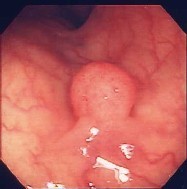

胃ポリープ:

健診の胃X線検査でポリープの疑い、内視鏡検査を施行すると小豆大の白色調の表面平滑なポリープを認めました。組織検査では過形成性ポリープの診断。このポリープは、大きくなったり癌になったりすることはありません。年に一度の検査で十分と思います。